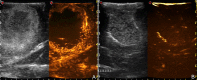

Introduction: Glioma surgery is aimed at obtaining maximal safe tumor resection while preserving or improving patient's neurological status. For this reason, there is growing interest for intra-operative imaging in neuro-oncological surgery. Intra-operative ultrasound (ioUS) provides the surgeon with real-time, anatomical and functional information. Despite this, in neurosurgery ioUS mainly relies only on gray-scale brightness mode (B-mode). Many other ultrasound imaging modalities, such as Fusion Imaging with pre-operative acquired magnetic resonance imaging (MRI), Doppler modes, Contrast Enhanced Ultrasound (CEUS), and elastosonography have been developed and have been extensively used in other organs. Although these modalities offer valuable real-time intra-operative information, so far their usage during neurosurgical procedures is still limited. Purpose: To present an US-based multimodal approach for image-guidance in glioma surgery, highlighting the different features of advanced US modalities: fusion imaging with pre-operative acquired MRI for Virtual Navigation, B-mode, Doppler (power-, color-, spectral-), CEUS, and elastosonography. Methods: We describe, in a step-by-step fashion, the applications of the most relevant advanced US modalities during different stages of surgery and their implications for surgical decision-making. Each US modality is illustrated from a technical standpoint and its application during glioma surgery is discussed. Results: B-mode offers dynamic morphological information, which can be further implemented with fusion imaging to improve image understanding and orientation. Doppler imaging permits to evaluate anatomy and function of the vascular tree. CEUS allows to perform a real-time angiosonography, providing valuable information in regards of parenchyma and tumor vascularization and perfusion. This facilitates tumor detection and surgical strategy, also allowing to characterize tumor grade and to identify residual tumor. Elastosonography is a promising tool able to better define tumor margins, parenchymal infiltration, tumor consistency and permitting differentiation of high grade and low grade lesions. Conclusions: Multimodal ioUS represents a valuable tool for glioma surgery being highly informative, rapid, repeatable, and real-time. It is able to differentiate low grade from high grade tumors and to provide the surgeon with relevant information for surgical decision-making. ioUS could be integrated with other intra-operative imaging and functional approaches in a synergistic manner to offer the best image guidance for each patient.